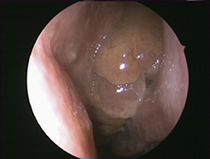

Polyposis nasi (Endoskopisches Bild, 0°-Optik)